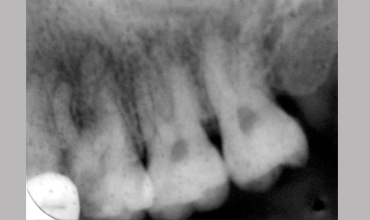

MB2

Management Of Maxillary First Molar With Mb 2 Canal